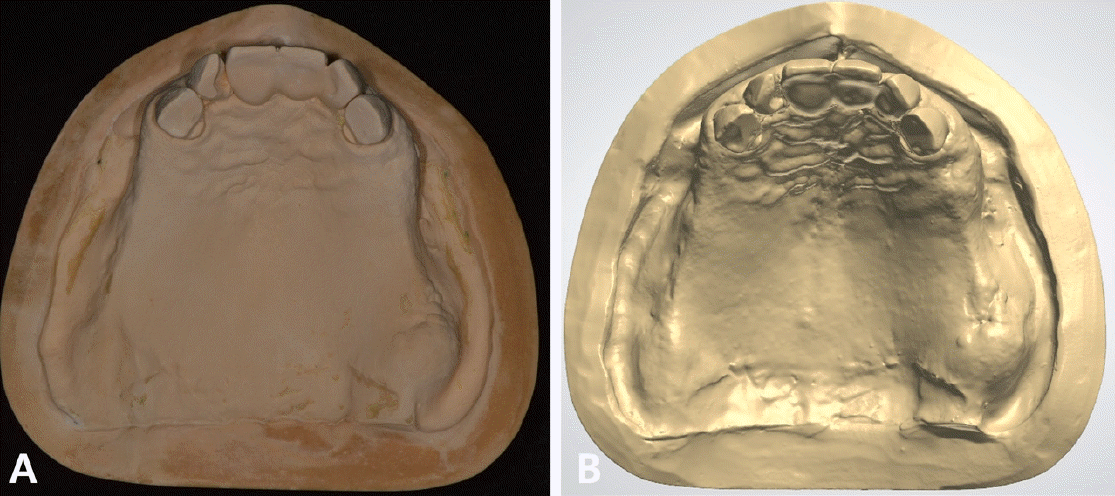

본 증례의 환자는 76세의 여성으로 상악 6전치만 잔존한 상태로 상악 가철성 국소의치의 제작을 위해 내원하였다. 상악은 6전치 중 상악 우측 견치와 좌측 견치의 상태는 동요도 및 파절 상태 없이 양호하였고, 상악 우측 측절치는 총생 상태였으며, 상악 우측 중절치와 상악 좌측 측절치를 이용해 3본 고정성 가공의치 형태로 상악 좌측 중절치의 수복이 되어 있는 상태였고, 상악 잔존 치조제의 상태는 중등도의 흡수 상태가 관찰되었다. 하악은 하악 좌측 제 2소구치는 잔존 치근 상태였다(Fig. 1). 상악의 경우엔 임시의치를 사용중이었고, 잔존 치근 상태인 하악 좌측 제 2소구치는 발거를 진행하였다. 전신병력으로는 B형 간염, 신장 투석, 파킨슨, 당뇨, 고혈압 및 협심증으로 다양한 약을 복용중이었고 비용 및 전신병력의 이유로 임플란트와 같은 수술적인 치료방법의 치료는 어려운 상태였다.상악은 양측 구치부의 결손이 있는 Kennedy Class I 으로 분류하고, 후방 결손부의 수복을 위해서 상악 가철성 국소의치의 제작을 진행하기로 결정하였다. 상악 가철성 국소의치의 디자인은 양측 상악 견치에 후방연장 국소의치의 유지를 위해 설면 레스트와 원심 유도면, 조직 언더컷으로 인해 RPA 클라스프를 설계하였고, 잔존 치아의 개수가 적어 주연결장치는 구개부를 대부분 피개하는 구개판형 연결장치를 설계하였다. 간접 유지의 역할을 위해 추가적인 설면 레스트의 부여를 고려하였으나 양측 측절치에 설면 레스트의 형성은 상악 우측 측절치의 총생 및 상악 좌측 측절치의 기존 보철 수복물로 인해 한계가 있었다(Fig. 2). 의치의 무게로 인한 탈락을 최대한 보완해보고자 금속 구조물의 제작을 코발트-크롬 합금보다는 보다 가벼운 특징을 가진 티타늄 합금(Ti-6Al-4V)을 이용하여 제작하기로 결정하였고, 7년 이내 요양급여를 통한 보험의치 적용을 받은 기록이 있어 비보험 진료로 진행하기로 하였다.해당 수복의 진행을 위해 양측 견치에 설면 레스트 시트를 구강 내 직접 형성 하였고 삽입 철거로를 고려하여 원심면의 치질 성형을 시행하였다(Fig. 2). 이후 개인 트레이를 제작 후 부가중합형 실리콘(Selection-K V.P.S, Shinhung Co., Seoul, Korea)를 이용해 기능인상채득을 시행하였다(Fig. 3). 이후 주모형을 제작하였고 제작된 주모형을 모델 스캐너(DOF Freedom HD, DOF Inc., Seoul, Korea)를 이용해 스캔하여 디지털 데이터를 형성하였다(Fig. 4). 이후 디지털 데이터를 이용하여 CAD 프로그램(3Shape dental system, 3Shape Inc., Copenhagen, Denmark)를 이용하여 금속 구조물을 디자인하였다(Fig. 5). 이후 해당 디자인된 금속 구조물을 선택적 레이저 용융 방식(SLM)의 3D 프린터(David 1.0, Merain Co., Incheon, Korea)를 이용하여 티타늄 합금(Ti-6Al-4V)으로 금속 구조물을 제작하였다. 또한 티타늄 합금과의 무게 비교를 코발트-크롬 재질의 금속 구조물도 티타늄 합금(Ti-6Al-4V)의 금속 구조물 제작에 사용한 동일한 CAD 파일을 이용하여 3D 프린팅을 통해 제작하였다.제작한 티타늄 합금(Ti-6Al-4V)과 코발트-크롬 합금의 금속 구조물의 후처리를 완료 후 주모형에 적합도 확인 및 무게 측정을 시행하였으며, 티타늄 합금(Ti-6Al-4V) 금속 구조물의 무게는 5.6g 이었고, 코발트-크롬 합금의 무게는 9.5g으로 티타늄 합금(Ti-6Al-4V)의 무게가 코발트-크롬 합금보다 41% 정도 더 가벼운 무게를 나타냈다(Fig. 6).제작된 티타늄 합금(Ti-6Al-4V) 금속 구조물의 적합을 환자 구강내에서 확인하였고, 이후 기록상을 제작하여 악간관계 기록을 채득 후 교합기에 부착하여 치아배열을 시행하였으며, 균일하게 중심교합 시 균일한 교합접촉을 이루는지 확인하였다(Fig. 7).

Figure 7.

Maxillomandibular relationship record using a recording base (A) and arrangement of artificial teeth (B)